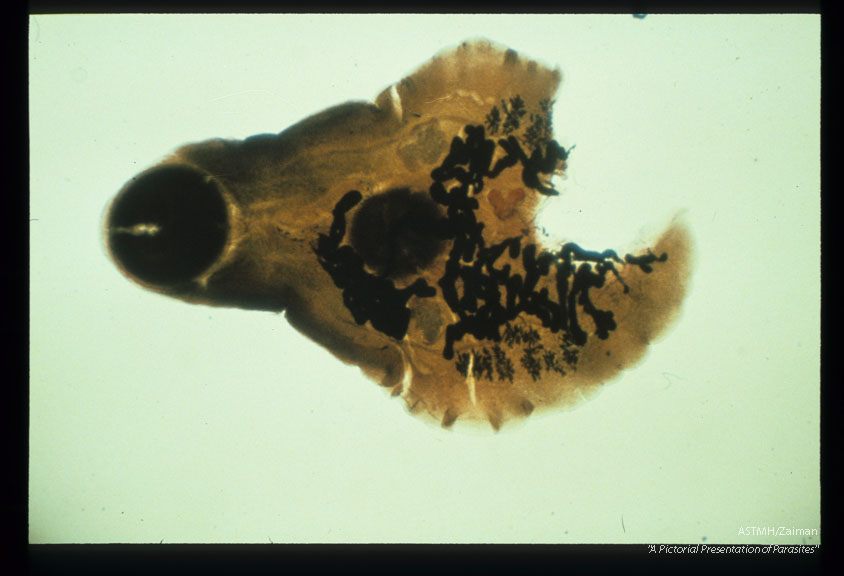

Adult trematode found in human pancreatic duct. Posterior amputated during dig section.

Eurytrema pancreaticum

Description: Adult trematode found in human pancreatic duct. Posterior amputated during dig section.